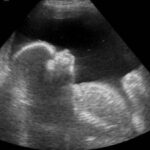

What is gestational diabetes? Gestational diabetes is diagnosed in a pregnant woman with no history of any kind of diabetes in her life. Like the general form, the gestational type is characterized by abnormally high blood glucose levels [1]. High glucose levels in the blood can be dangerous both for the mother and child. Gestational diabetes is usually diagnosed later … [Read more...] about Gestational Diabetes

Placental Abruption Definition Placental abruption, or abruptio placentae, is a pregnancy complication in which the placenta peels away from the lining of the uterus prior to delivery. [1] Its severity depends on whether the separation is partial or complete. The abruption hampers the oxygen and nutrient supply to the baby, [2] sometimes causing … [Read more...] about Placental Abruption